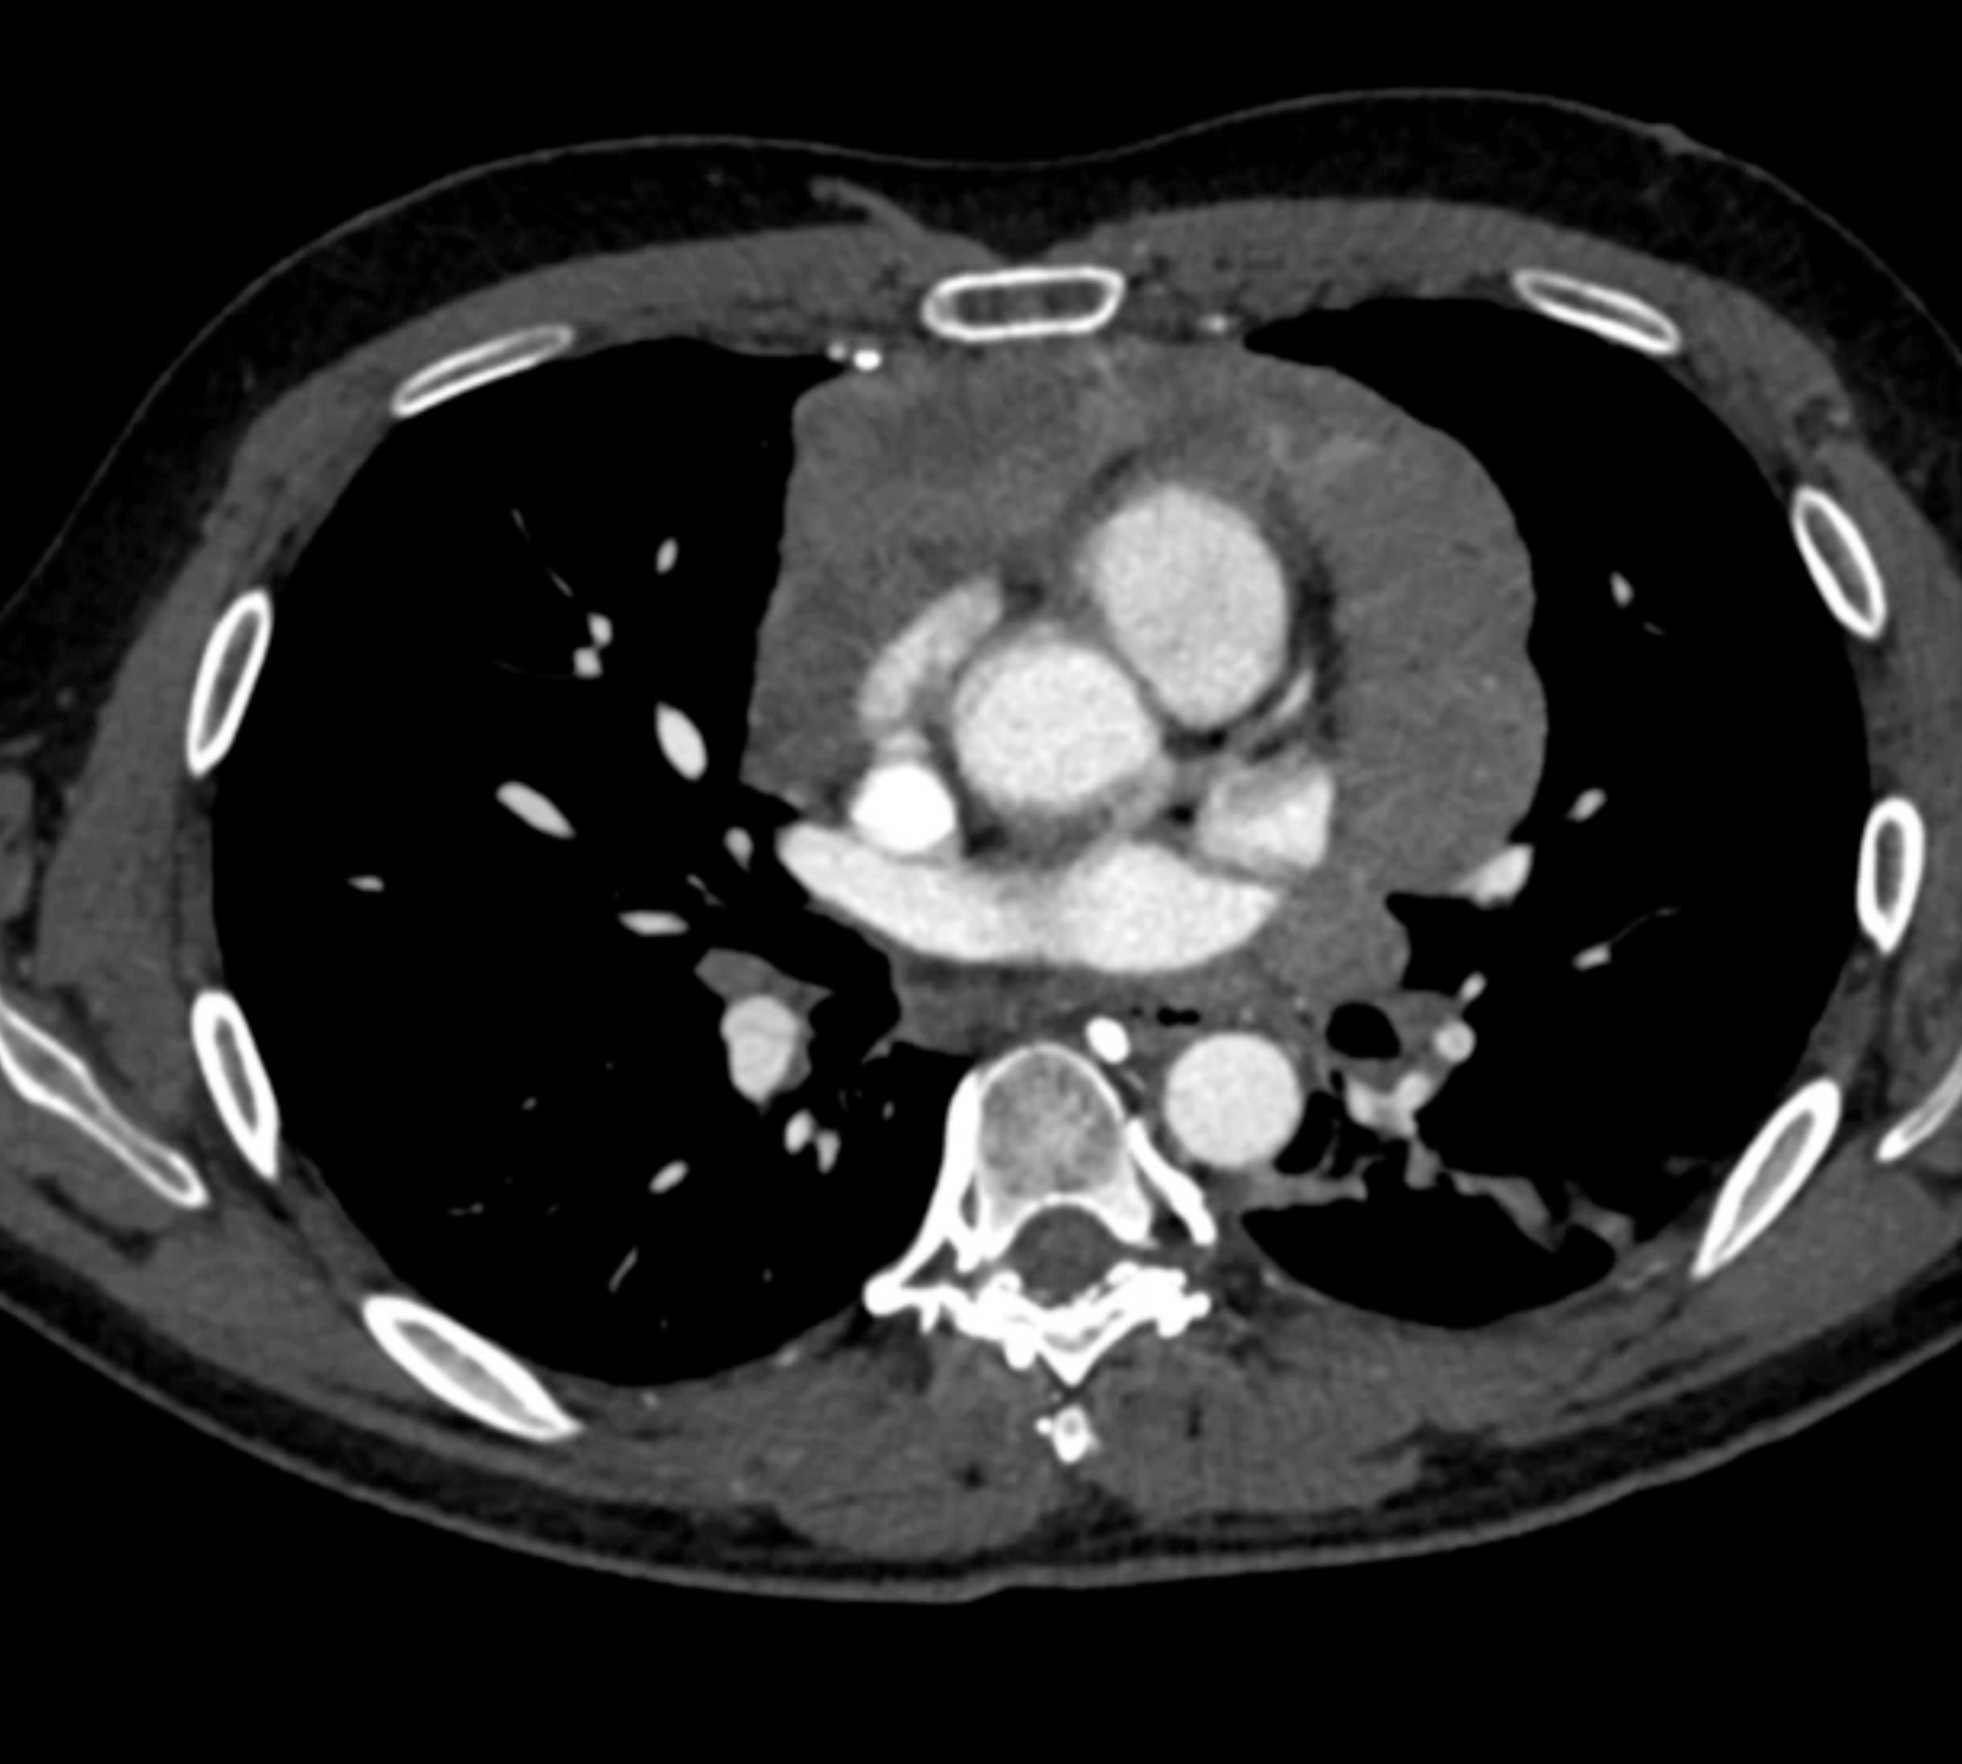

Thymic Carcinoma